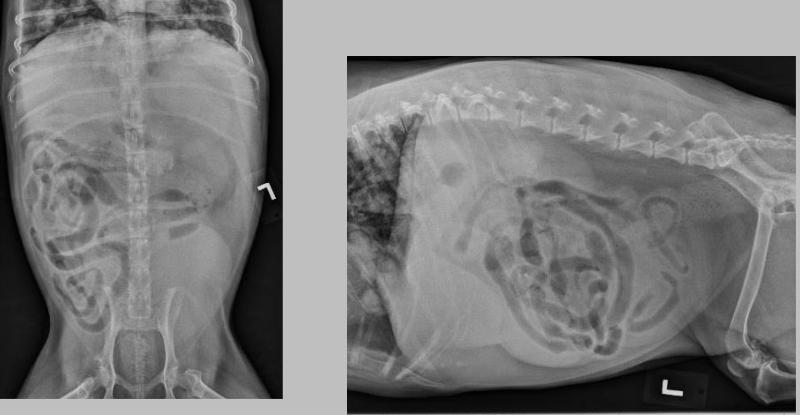

what is going on here?

you can see tubular soft tissue opacities along the caudal lateral body wall and loss of serosal detail caudally, this is pyometra

what is this?

pyometra apparently...I struggle seeing it